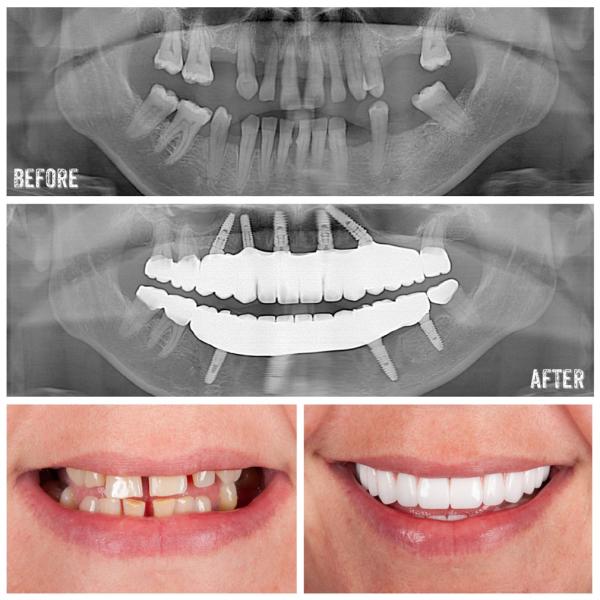

Why Is Antalya the Best Place for Dental Implants?

Antalya has earned a reputation for dental implants due to:

- Experienced Dentists: Many Turkish dentists have extensive training and experience in implantology, often with international certifications.

- Affordable Prices: Dental implants in Antalya are much more affordable due to lower operating costs, without compromising quality.

- High-Tech Clinics: Many dental clinics in Antalya are equipped with the latest technology, ensuring precise and efficient implant procedures.